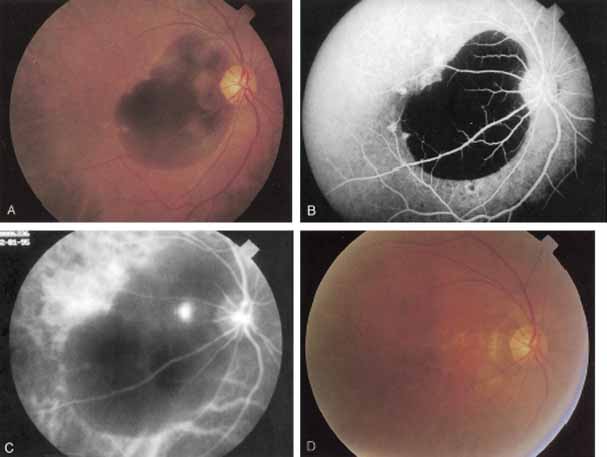

An important report by Chang and co-workers27 lends support to the rationale for interpreting the hyperfluorescence seen on ICG angiography as CNV. In this clinicopathologic study, a patient was identified who had experienced subretinal hemorrhage with early signs of occult CNV on fluorescein angiography (Fig. 4A). Fluorescein angiography demonstrated blocked fluorescence (Fig. 4B). The ICG study, however, demonstrated late staining in a well-circumscribed fashion, which the authors interpreted as a “plaque” of occult CNV (Fig. 4C). When the patient died, this area was evaluated and studied histopathologically and compared with the picture seen on ICG angiography. The area of hyperfluorescence on the ICG study corresponded precisely to a thin layer of fibrovascular tissue beneath the pigment epithelium and neurosensory retina, confirming that the late-staining tissue imaged with ICG angiography was truly a neovascular membrane (Fig. 4D).

With this clinical diagnostic and histopathologic information available, pilot studies were performed to determine the practicality of using ICG angiographic guidance in the treatment of occult CNV. Slakter and associates28 performed laser photocoagulation treatment on 79 eyes with occult CNV. The occult CNV was successfully eliminated in 57% of patients who underwent ICG-guided treatment (Figs. 5 and 6). The authors found the success rate to be higher (66%) for patients with CNV not associated with PEDs than for those with PEDs (43%). Visual acuity improvement or stabilization was achieved in 57% of all patients. Recurrences were more frequent and more difficult to control in those patients who had associated PEDs on initial clinical presentation. Additional independent studies have reported similar diagnostic and treatment outcomes with the use of ICG angiography in patients with occult CNV.29,30